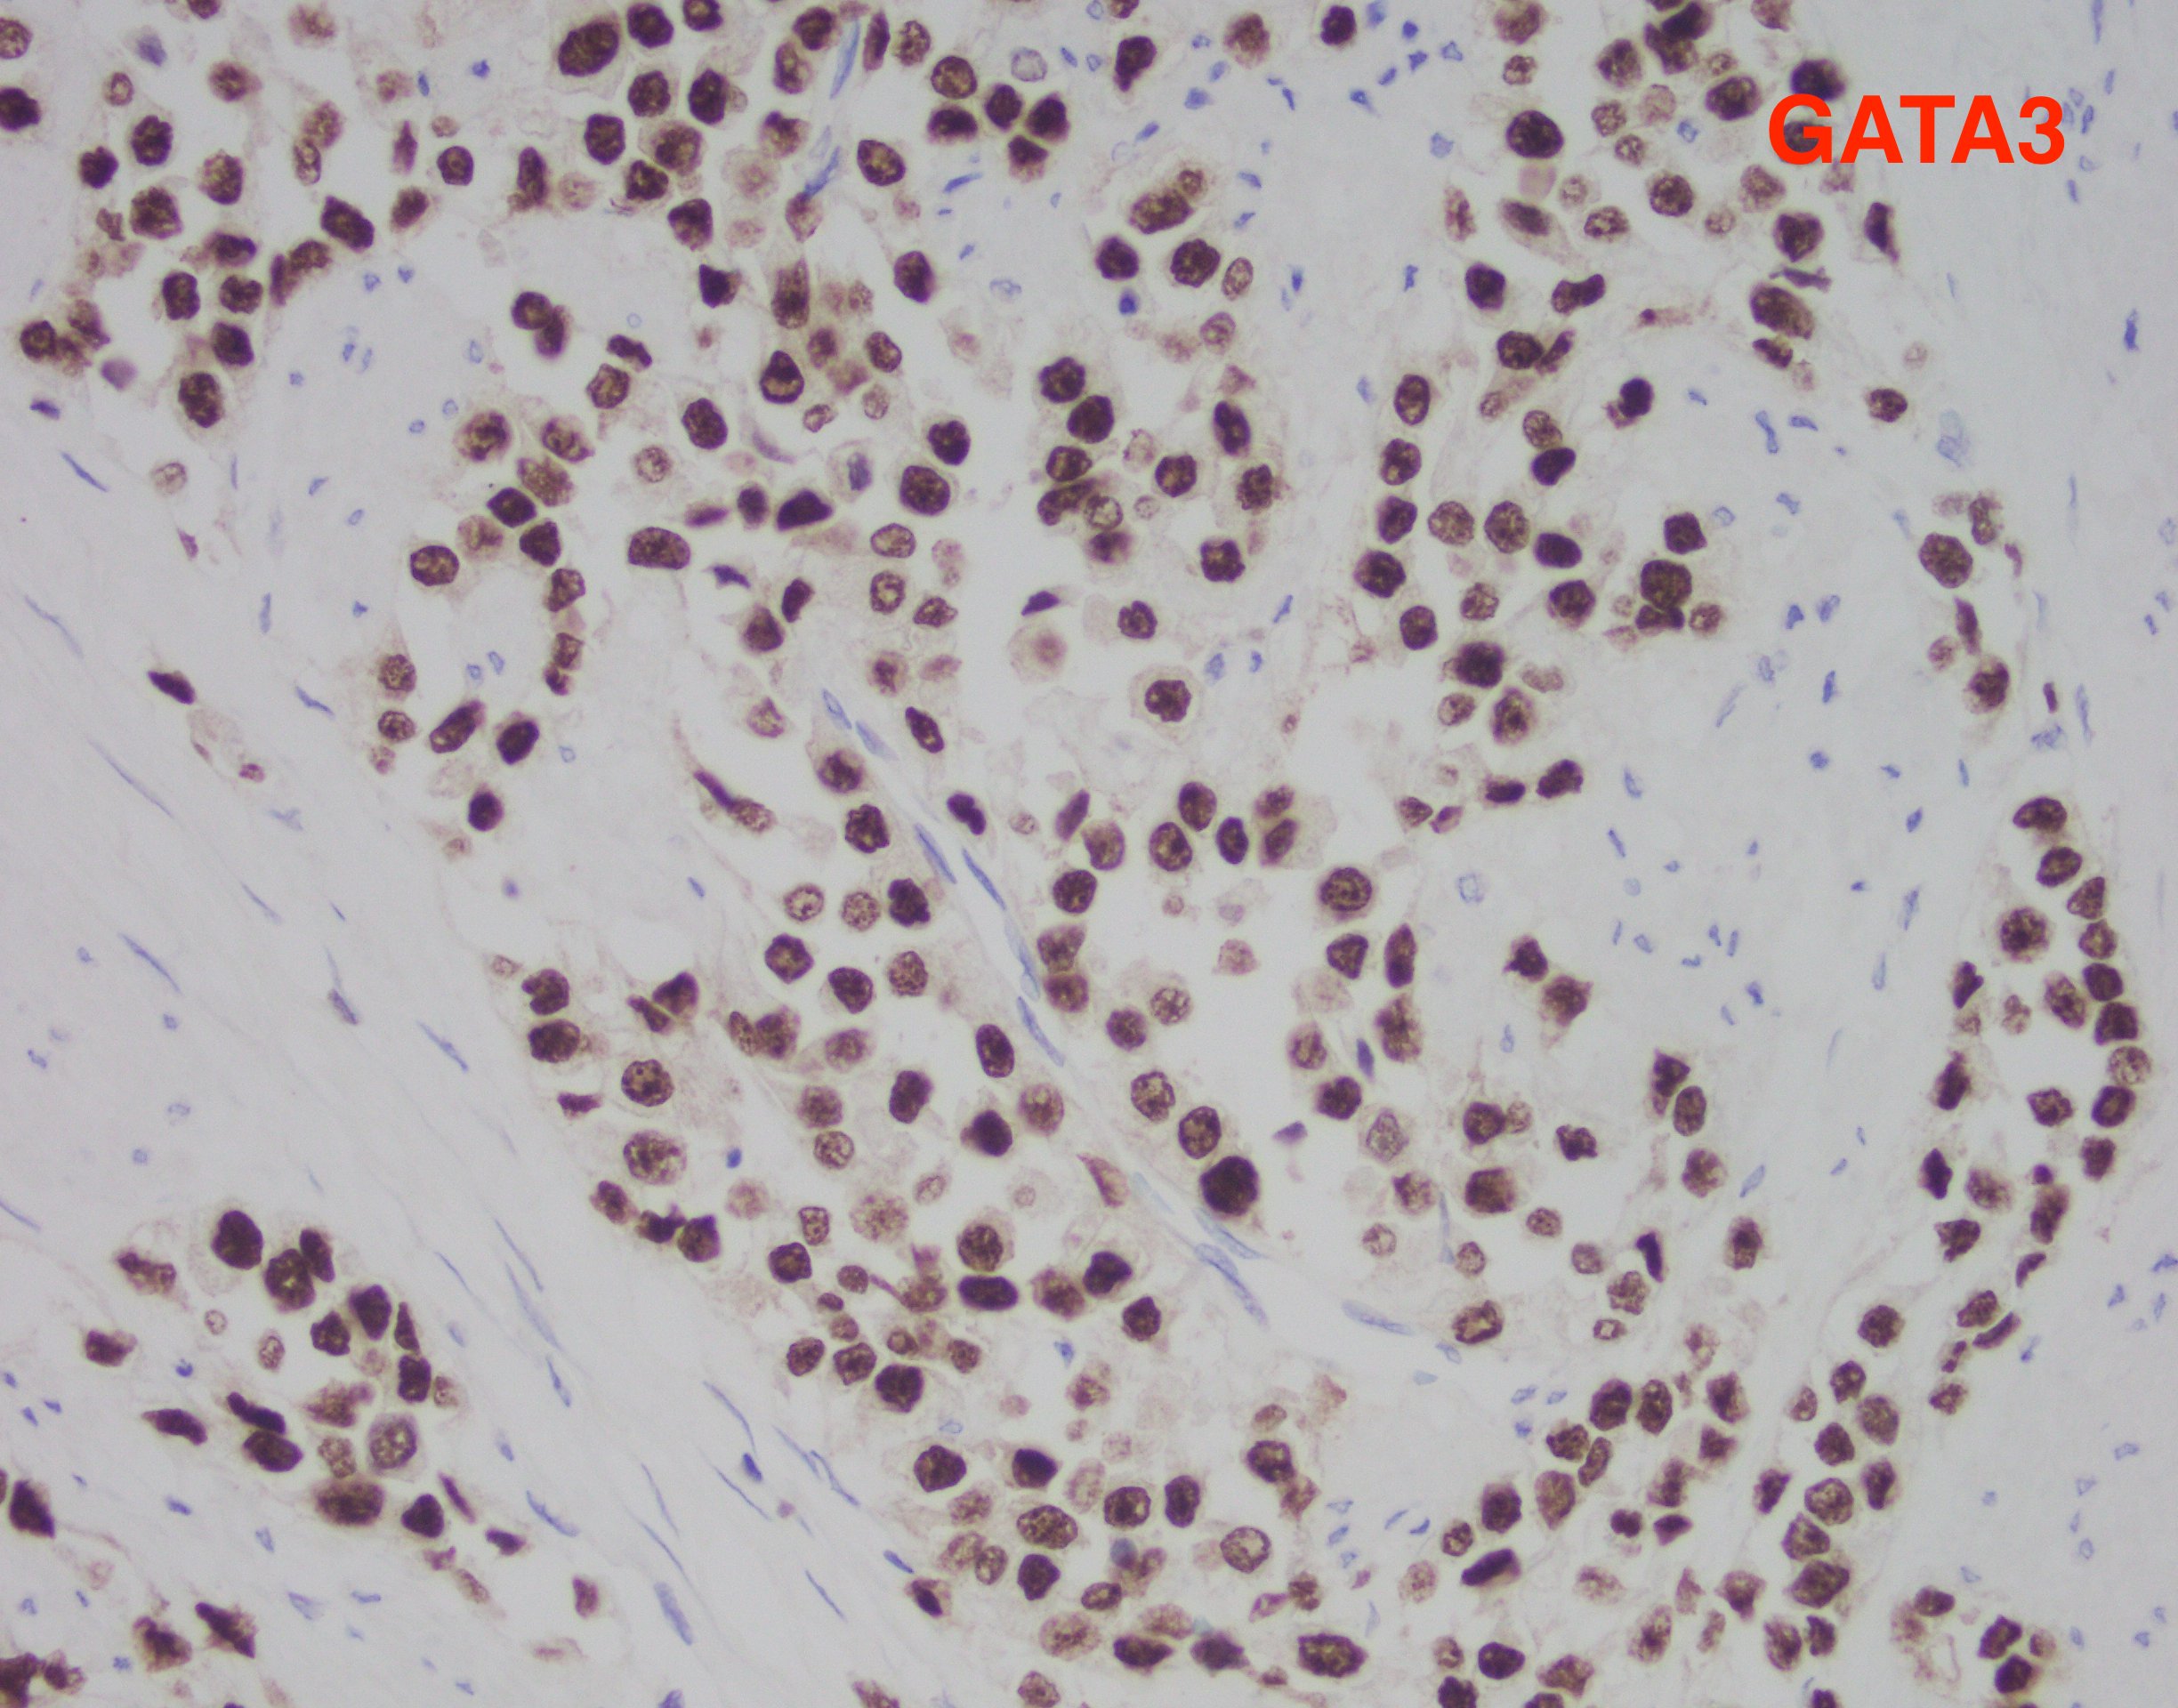

The findings in this case show a diffuse, infiltrative, and discohesive tumor extending into the perivesical adipose tissue. There is extensive perineural and lymphovascular invasion. Focal areas show urothelial carcinoma in situ. Tumor cells have eosinophilic cytoplasm, and nuclei are eccentrically located with focal signet ring cell features. Staining with p63 and GATA3 was performed and shows positivity in both stains.

These features are all consistent with the plasmacytoid variant of urothelial carcinoma. Typically, this variant grows in a linitis plastica-like manner. Tumor infiltration is diffuse, in single cells or cords. Characteristically, tumor cells exhibit eccentric nuclei and/or signet ring cell morphology. Of note, these tumors stain similar to usual urothelial carcinomas, but also strongly express CD138 and lose E-cadherin expression. Most tumors are locally advanced at the time of diagnosis and are highly aggressive.